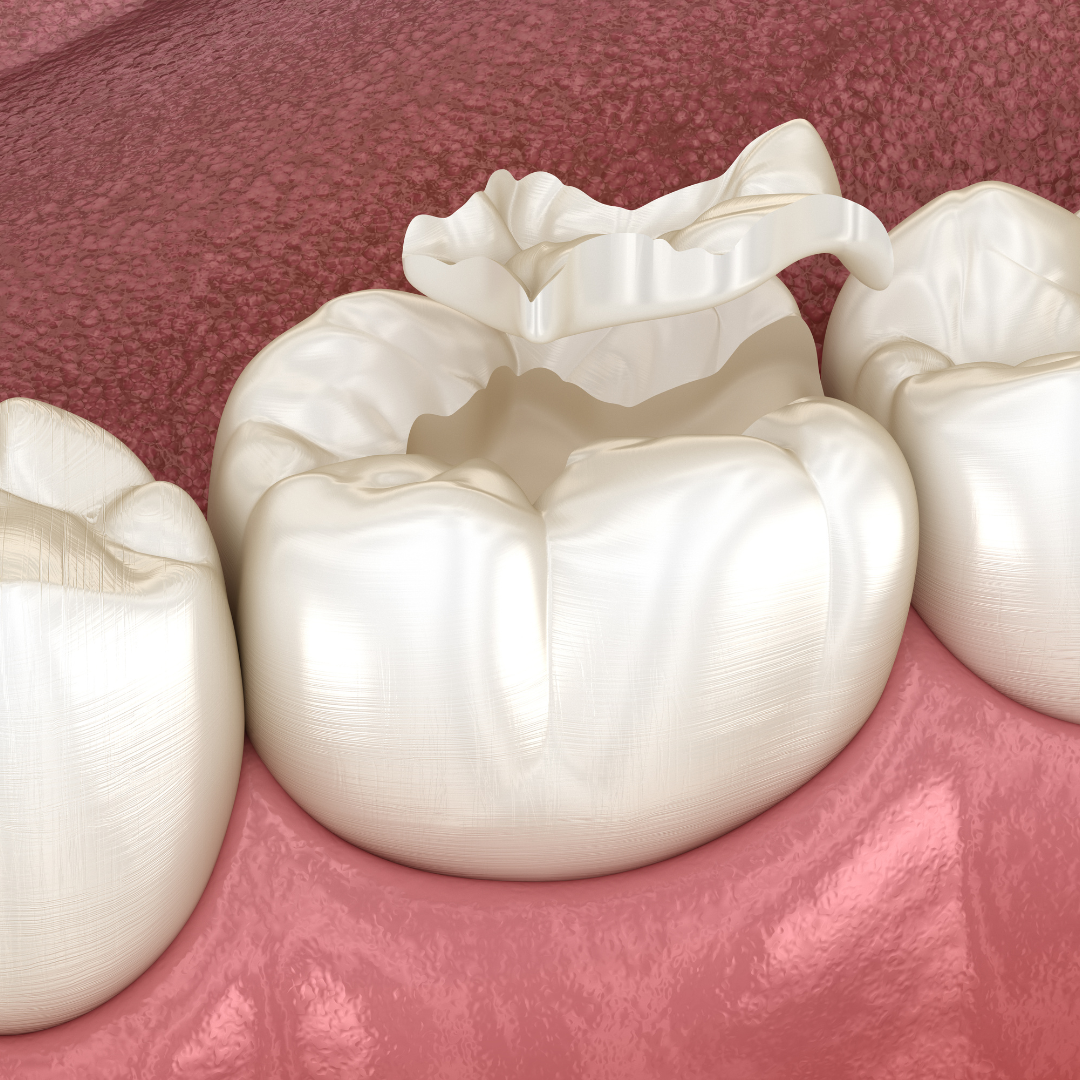

Also known as indirect fillings, these treatments

Restorative dental treatments aim to restore damaged or decayed teeth to their natural function and appearance.